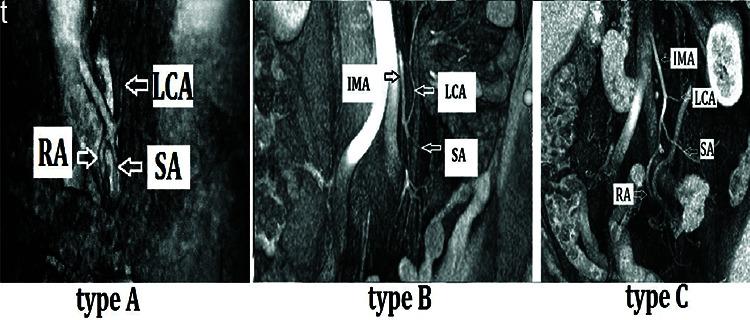

Pre-operative MDCTA 3D reconstructions defined the left colic and sigmoid artery anatomy and guided operative planning. The intraoperative ICG angiography resulted in a change of the planned lines of resection in seven patients (26%). The rate of postoperative anastomotic leaks in this study was 0% (0/27), compared to a leak rate of 6.8% at our institution in the preceding two years.

术前 MDCTA 3D 重建定义了左结肠和乙状结肠动脉解剖结构,并指导手术计划。术中 ICG 血管造影导致 7 例(26%)患者改变了计划的切除线。本研究中术后吻合口漏的发生率为 0%(0/27),而我院前两年的吻合口漏发生率为 6.8%。